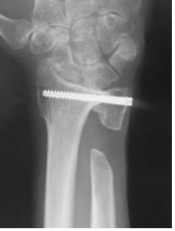

橈骨遠位端骨折に対する鏡視併用手術

橈骨遠位端骨折は頻度の高い骨折の一つで、特に関節内骨折については関節鏡を併用し従来のX線のみでは整復が不十分な関節面の整復を行っています。

骨折治療に加えて骨折の予防に骨粗しょう症の治療の導入も積極的に行っています。

術後